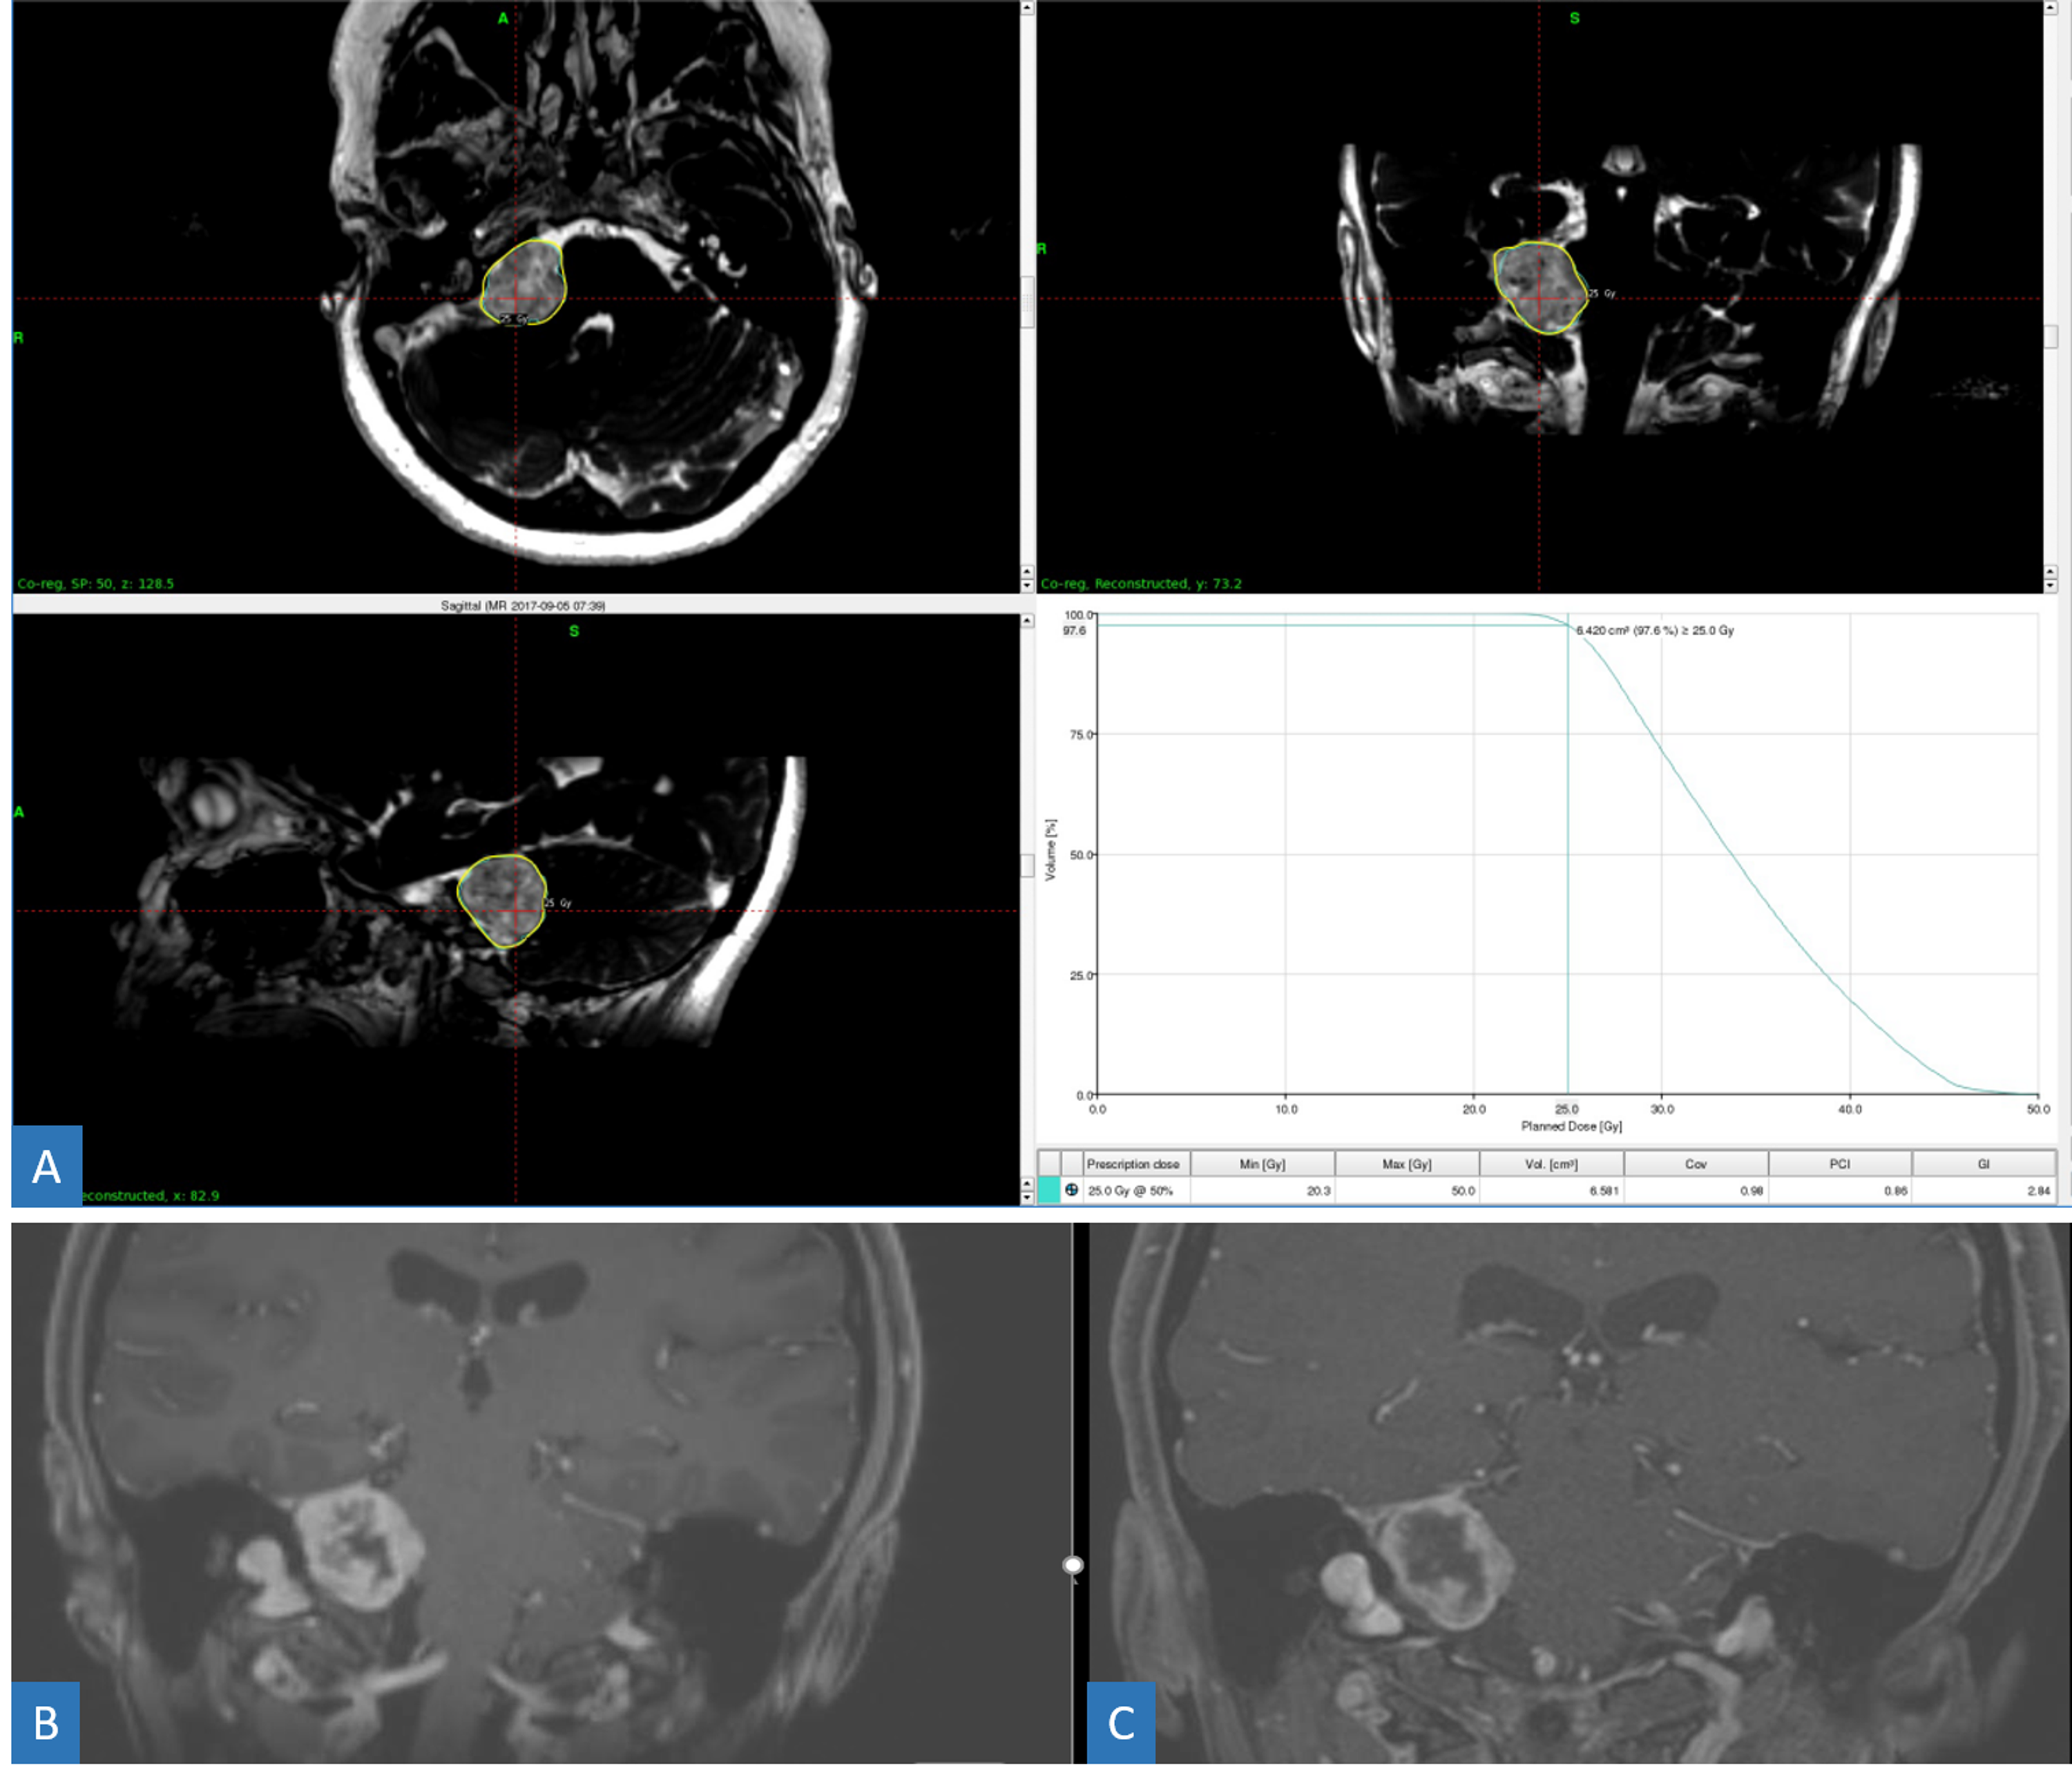

Source: redjournal.org

Source: cureus.com